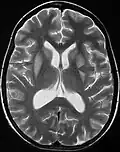

Mielinolisis central pontina -

Resonancia que muestra aumento de la intensidad de la imagen bilateral y simétrica a nivel del caudado (flecha pequeña), putamen (flecha larga) con extensión hasta el globo pálido, sugerente de mielinólisis extrapontina